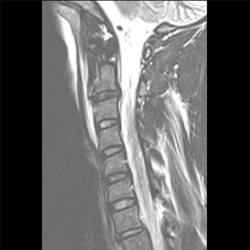

Cervical Spine Trauma Case 01